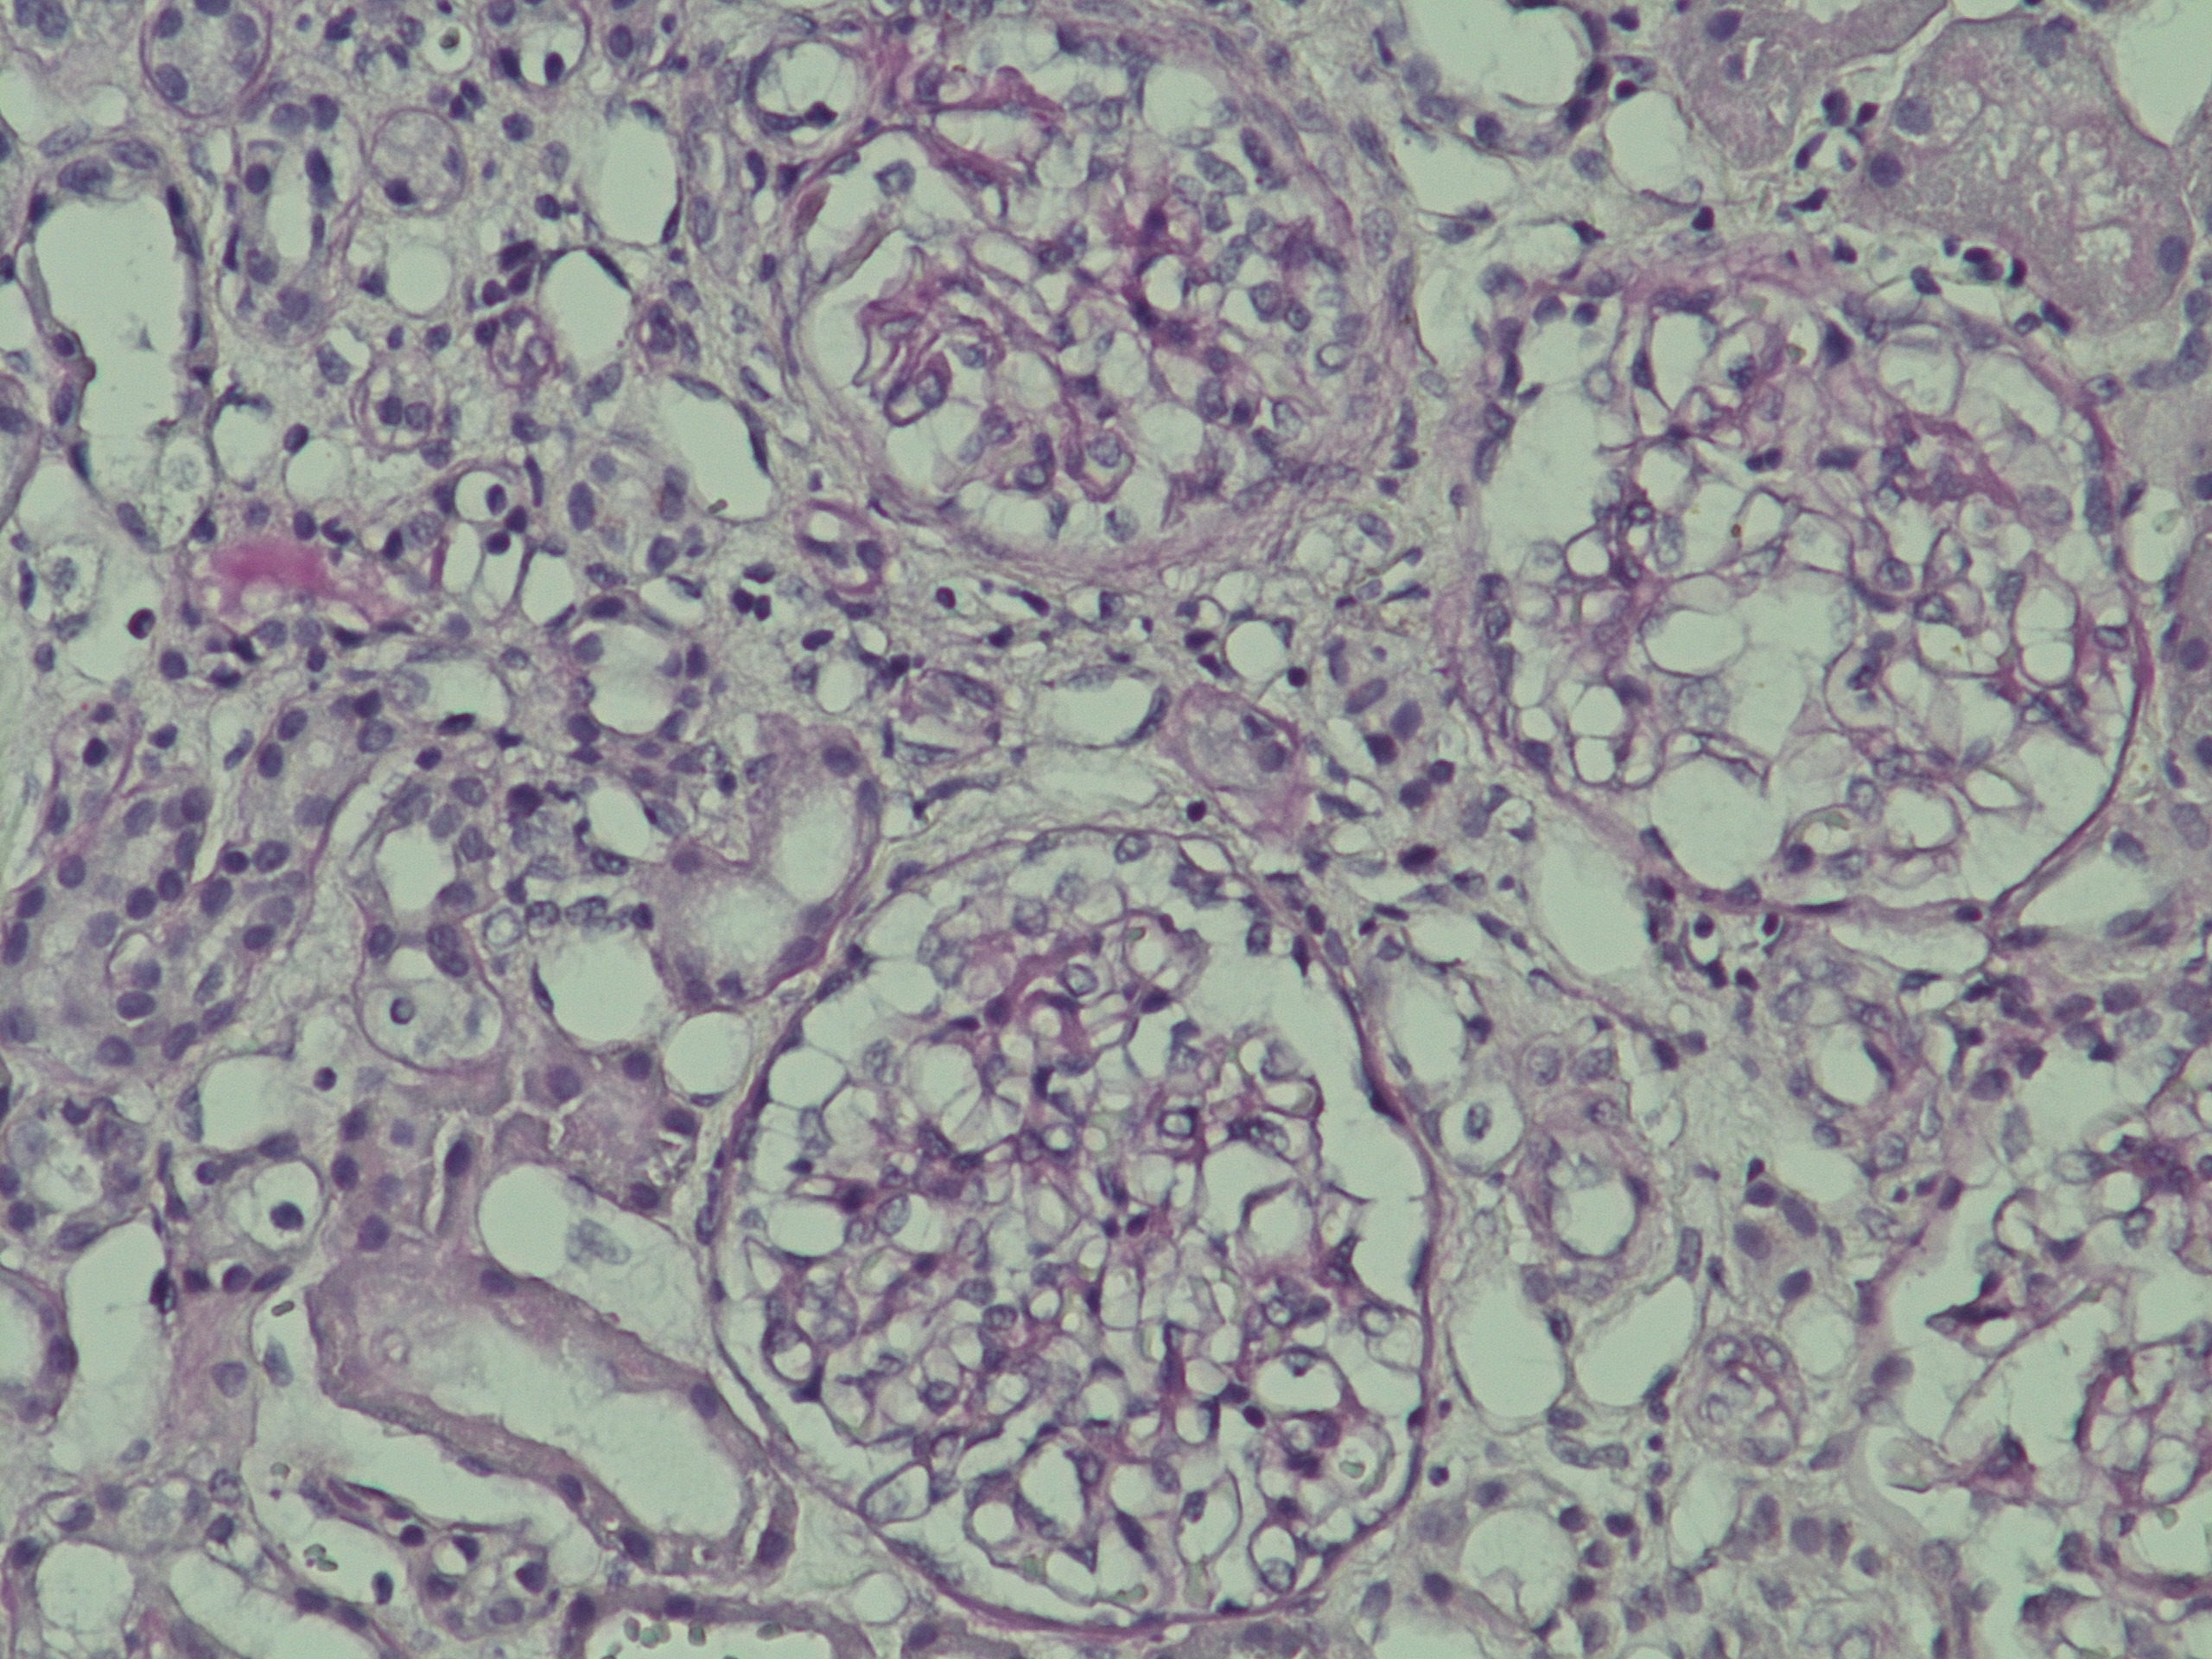

С целью определения гормональной активности образования был выполнен супрессивный тест с 1 мг дексаметазона: кортизол плазмы на следующее утро в 08:00 – 4,03 мкг/дл (норма <1,8 мкг/дл), АКТГ – 0,55 пмоль/л (1,6–13,9 пмоль/л), метанефрин в суточной моче – 373 мкг/сут (норма <320 мкг/сут), норметанефрин в суточной моче – 464 мкг/сут (норма <390 мкг/сут). Биохимические показатели: глюкоза крови натощак – 6,8 ммоль/л, общий холестерин – 4,9 ммоль/л. С учетом незначительного повышения в суточной моче уровня метанефрина и норметанефрина на фоне большого размера образования (41 × 42 × 56 мм) феохромоцитома была исключена. Пациент был направлен в ФГБУ РНИОИ с диагнозом “адренокортикальный рак, глюкокортикоид-продуцирующий”. Была выполнена лапароскопическая адреналэктомия слева. Заключение гистологического исследования удаленного образования: “Морфологическая картина более всего соответствует феохромоцитоме, дискомплексированный вариант, с очагами некроза, кровоизлияний, инвазия стенки сосудов (рис. 2, 3). Результат иммуногистохимического исследования: S-100 – отрицательная реакция, Сhromogranin A – умеренно выраженная цитоплазматическая реакция в клетках опухоли, Synaptophysin – слабо выраженная цитоплазматическая реакция в клетках опухоли, Ki-67 – позитивная ядерная реакция в единичных клетках опухоли. Заключение: морфологическая картина и иммунофенотип более всего соответствуют феохромоцитоме”.

Рис. 2. Гистологическая картина удаленного образца надпочечника (окраска гематоксилином и эозином, ×120). Дискомплексированный вариант феохромоцитомы. Особо следует обратить внимание на неравномерную секреторную активность клеток коры надпочечника (клубочковая зона), активные светлые зоны с выраженным полнокровием.

Рис. 3. Гистологическая картина удаленного образца надпочечника (окраска гематоксилином и эозином, ×120). Феохромоцитома злокачественная с умеренным инвазивным ростом в кору надпочечника (слева направо), сосуды, некрозы и перивазарная воспалительная инфильтрация.